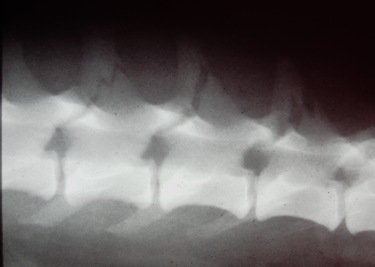

Radiographs of the lumbar spine are shown below (taken with sedation).

What is the diagnosis?